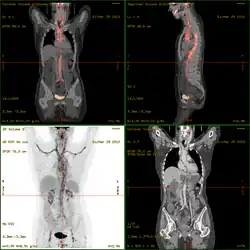

Severe vasculitis of the major vessels, displayed on FDG-PET/CT

• 18F-fluorodeoxyglucose positron emission tomography/computed tomography (FDG-PET/CT)has become a widely used imaging tool in patients with suspected Large Vessel Vasculitis, due to the enhanced glucose metabolism of inflamed vessel walls.[38] The combined evaluation of the intensity and the extension of FDG vessel uptake at diagnosis can predict the clinical course of the disease, separating patients with favourable or complicated progress.[39]